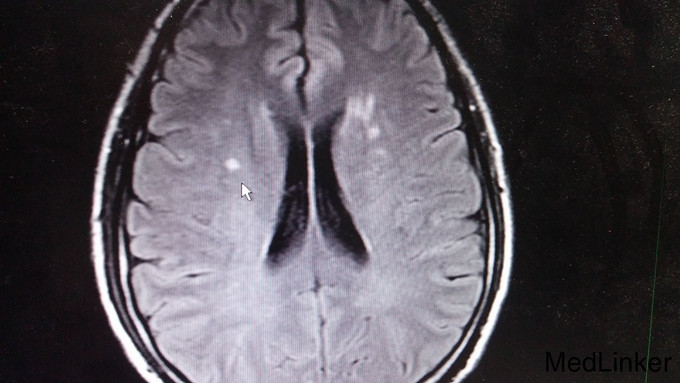

双侧向内侧凝视,左眼外展不能。辅查: 1. 血管炎指标五项、抗核抗体谱、抗心磷脂抗体未见明显异常,血沉27mm/h。 2. 头颅MRI:双侧放射冠区、左侧基底节区及右侧小脑半球多发梗塞灶(右侧小脑半球亚急性期脑梗塞)。

头晕、头痛好转,左眼外展受限同前。讨论: 1.患者左侧外展 受限,定位于左侧脑干,MRI示右侧桥脑腔隙性梗死,非责任病灶; 2.一般梗塞不会引起头痛,住院前10天有腮腺炎病史,尽管血管炎指标阴性,仍考虑血管炎而非脑梗的可能性大。